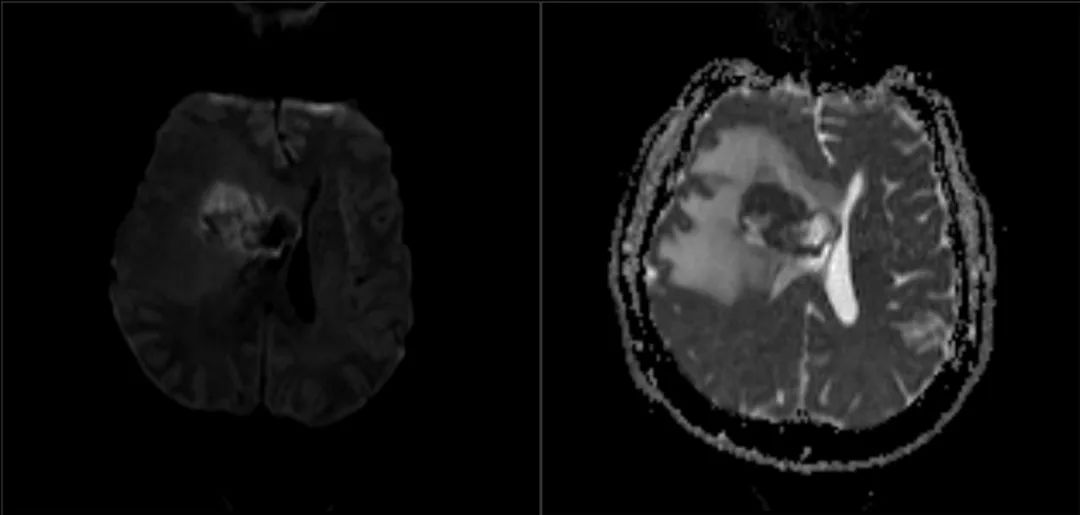

患者为55岁男性,因“跌倒频率增加和左侧肢体无力1周余”就诊。 3年前患者曾于外院行肺癌切除术,但患者后来失访,且无法明确癌变性质和分期。 入院时神经系统查体无异常。 外院头颅CT见颅内出血灶,胸腹盆腔CT未见异常。 立体定向颅内病变活检提示肿瘤为低分化转移癌,细胞标志物检测考虑鳞状细胞癌。

术后患者安返神经ICU。 术后使用地塞米松并于1周内迅速减量撤药。 使用左乙拉西坦500mg bid预防性抗癫痫。 术后第1天复查MRI见肿瘤近全切。

最终病理与活检结果一致,均为转移性低分化癌。 术后第5天患者出院回家,无神经功能障碍,残余肿瘤计划行立体定向放疗,同时建议患者肿瘤科随诊,以处理系统性病变。